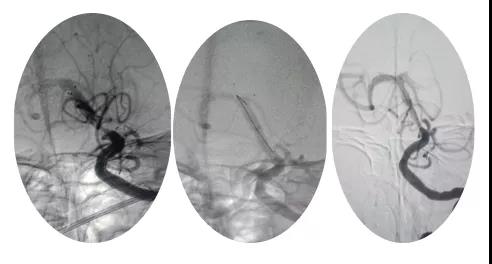

18:30手術(shù)開(kāi)始,造影為基底動(dòng)脈閉塞,與患者家屬充分溝通,患者家屬同意給予介入取栓治療。共取栓2次,取出少量暗紅色血栓塊。造影示:基底動(dòng)脈有重度狹窄,結(jié)合患者病情演變及造影結(jié)果,考慮為動(dòng)脈粥樣硬化性狹窄。根據(jù)患者造影結(jié)果,目前單純?nèi)∷o(wú)法達(dá)到預(yù)期效果,決定給予基底動(dòng)脈支架植入術(shù)。根據(jù)患者基底動(dòng)脈直徑選擇3.0*13mm apollo球擴(kuò)支架,支架植入后造影示狹窄消失。

支架植入后患者神志轉(zhuǎn)清,四肢均可活動(dòng),左側(cè)肢體活動(dòng)略差于右側(cè),收入神經(jīng)內(nèi)四科病房進(jìn)一步治療。術(shù)后第三天患者神志清,四肢活動(dòng)基本正常,住院5天轉(zhuǎn)入當(dāng)?shù)蒯t(yī)院治療。?